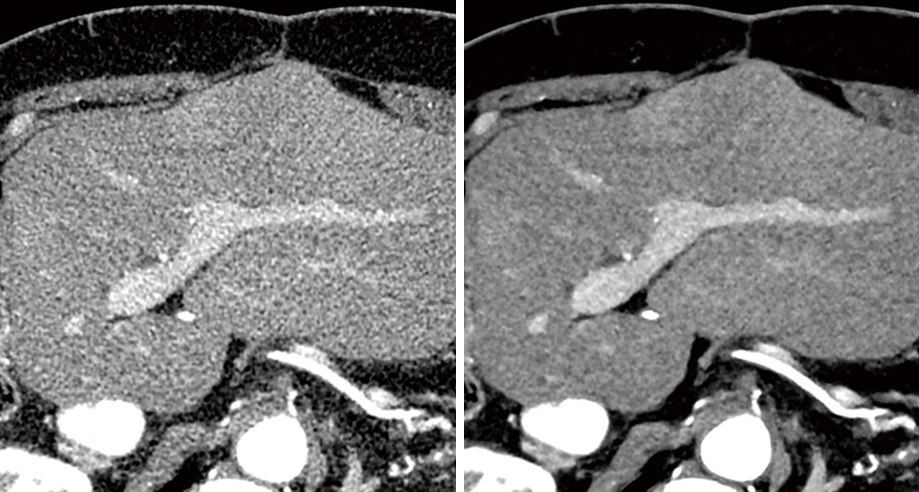

従来技術(左)とAiCE(右)の画質比較

「AiCE」は、CTのノイズを低減しながら高精細画像を得られる最新技術です。これにより、健康診断などで使用される胸部レントゲン撮影とほとんど変わらない低いX線量で、より精密な検査を可能にしました。一般的なノイズ低減処理では画像の細かい描写力が低下してしまうことがありますが、「AiCE」はCTが持つ画像の精細さを引き出しつつ、高いノイズ低減効果を実現。さらに、低コントラスト領域でも安定した画質改善が得られることが大きなメリットです。